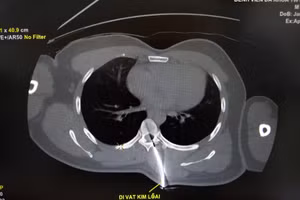

Hy hữu trường hợp bệnh nhân mang cả mũi dao cắm vào cột sống vào phòng mổ 09/04/2021 09:15 GD&TĐ - Bệnh viện Đa khoa Trung ương Cần Thơ cho biết, các bác sĩ bệnh viện vừa phẫu thuật cấp cứu thành công một trường hợp bệnh nhân bị mũi dao đâm vào cột sống